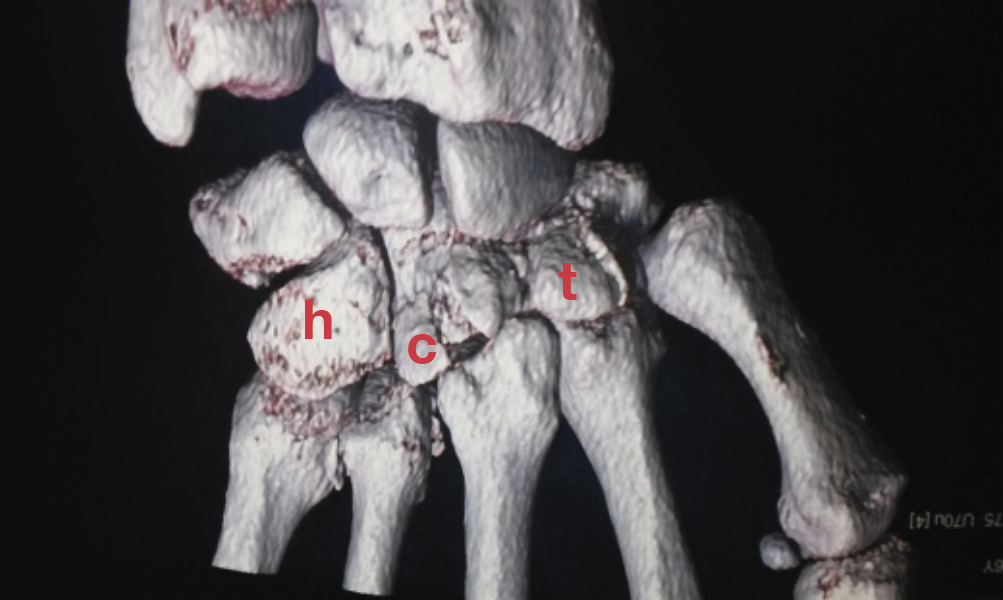

La radiographie montre une probable fracture de la base du 4e métacarpien sur l’incidence de face. Le scanner confirme une fracture comminutive de la base de M4, du capitatum, du trapézoïde et une discrète subluxation vers l’arrière de la base de M3.

Le trapézoïde est touché dans environ 0,2 % des cas. Les fractures de l’hamatum (h) sont également rares et accompagnées d’une fracture et/ou une subluxation du 4

et du 5

métacarpien.